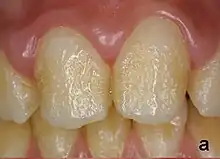

Enamel hypoplasia can take a variety of forms, but all types are associated with a reduction of enamel formation due to disruption in ameloblast production.[1] One of the most common types, pitting enamel hypoplasia (PEH), ranges from small circular pinpricks to larger irregular depressions.[2] Pits also vary in how they occur on a tooth surface, some forming rows and others more randomly scattered.[3] PEH can be associated with other types of hypoplasia, but it is often the only defect observed.[4] Causes of PEH can range from genetic conditions to environmental factors, and the frequency of occurrence varies substantially between populations and species, likely due to environmental, genetic and health differences. The most striking example of this is in Paranthropus robustus, with half of all primary molars, and a quarter of permanent molars, displaying PEH defects, thought to be caused by a specific genetic condition, amelogenesis imperfecta.[1]

Each pit is linked to the ceasing of ameloblasts at a particular point in enamel formation. Sometimes, only a couple of ameloblasts stop forming enamel, leading to small PEH defects, with large pits forming when hundreds of these enamel-forming cells stop production.[6] This does not occur in other forms of enamel hypoplasia, such as linear and plane-form, in which all ameloblast activity is affected.[4] Typically with PEH described in archaeological reports, researchers can not specify a cause, with a non-specific stress often concluded. However, in modern clinical studies it is often possible to suggest a cause and these can include the following conditions:[1]